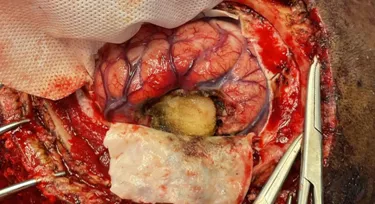

We operated on him under General Anesthesia, a left Parietal Craniotomy was done and the dura overlying the tumor was gently laid open and dissected away from the tumor. To our surprise, on the table the tumor was highly vascular had no clear margins contradicting the MRI findings. So our anaesthesia team started a blood transfusion and the surgical team gradually moved to a piecemeal approach and excised the tumor. A near total excision was achieved and the cavity was packed with hemostatic agents as there was profuse bleeding towards the end of dissection.

We were able to achieve hemostasis and dural reconstruction was done with G Patch. The overlying dura was excised and sent for biopsy alongside the tissue.

The excised tumor tissue and the dura. Dura reconstructed with a G Patch